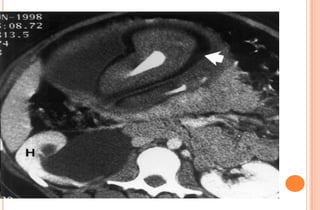

PHOTOS OF CT EVALUATION OF

PREGNANT WOMAN WITH TRAUMA– CT

SCANS DONE AS A PART OF INVESTIGATIONS

DONE IN EMERGENCY --- MATERNAL HEAD

AND ABDOMEN AS PER NEED OF INDIVIDUAL

CASE ---WITHOUT FEAR OF X RAYS

EXPOSURE TO FETUS IN UTERO